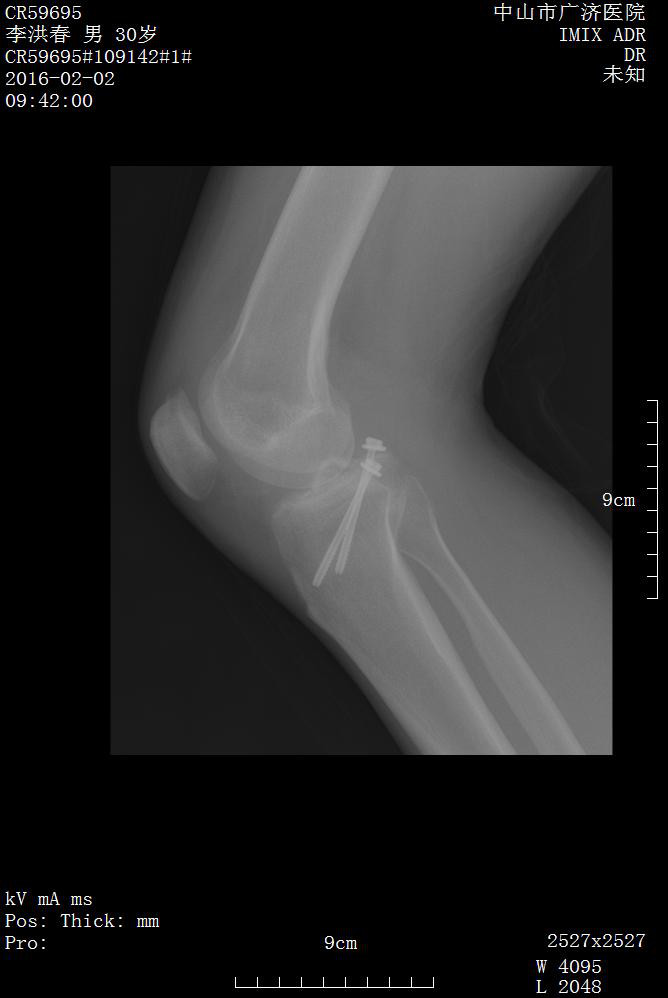

手法復位影像片:

1.右膝關節后交叉韌帶止點撕脫性骨折(2 型)

2 型及以上,或合并其他韌帶損傷時,需要關節鏡或開放性手術治療。外科手術介入和修復可以防止關節慢性不穩定性變,以及繼發性關節炎。

有移位的PCL脛骨止點撕脫性骨折,應盡早手術復位內固定修復,以達到交叉韌帶解剖重建和等長重建, 骨性愈合,恢復膝關節的穩定性